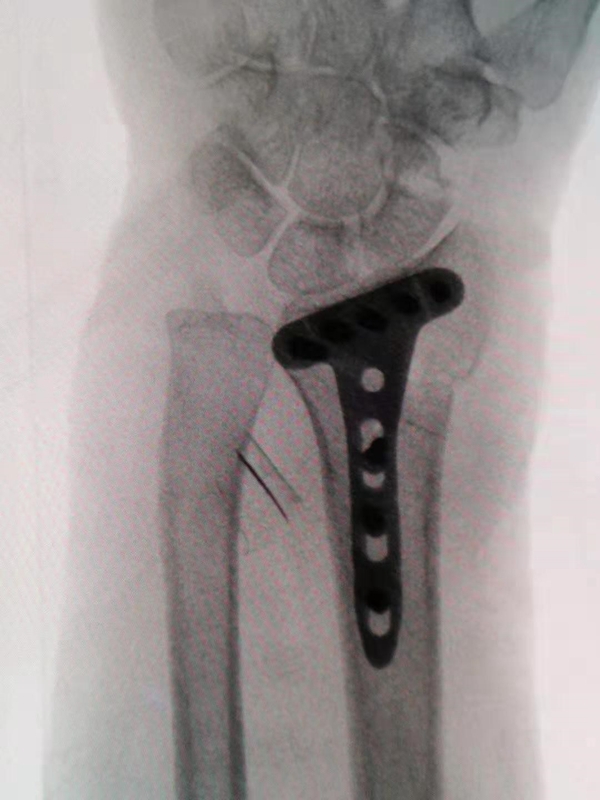

尺桡骨远端功能上分为三柱;

桡骨远端包含桡侧柱及中柱;

尺骨远端和三角纤维软骨复合体构成尺侧柱。

图1 前后位X线显示尺桡骨远端三柱结构,R为桡侧柱,I为中柱,U为尺侧柱,P为桡骨远端基底干骺端

桡侧柱的骨折常包括以较大的、骨折线累及干骺端的茎突骨块居多,肱桡肌的牵拉常导致骨折块桡侧移位和关节面移位的加重。

中柱的骨折常导致掌侧缘、背侧壁、尺背侧部分及中间游离骨块;掌侧缘骨块及尺背侧部分骨块常累及大部分月骨关节面和全部的乙状切迹,是两个关键骨块。

中柱掌侧缘骨块是桡月短韧带和掌侧下尺桡韧带止点,累及这一部分的骨折为:(1)掌屈压缩导致的掌侧不稳定伴掌侧移位、中柱短缩骨折(掌侧Batton骨折);(2)背伸压缩导致的轴向不稳定,腕骨的背侧移位,中柱背侧骨块和/或中间游离关节面骨块。

尺骨和三角纤维软骨复合体构成尺侧柱,尺侧柱是下尺桡稳定和前臂旋转运动的重要组成部分。下尺桡韧带的浅层和深层分别止于尺骨茎突尖部和尺骨小凹。桡骨远端骨折后桡骨的短缩、背侧移位和尺偏角的减小都会导致三角纤维软骨复合体和尺骨茎突的压力增加,导致继发的尺侧柱损伤。